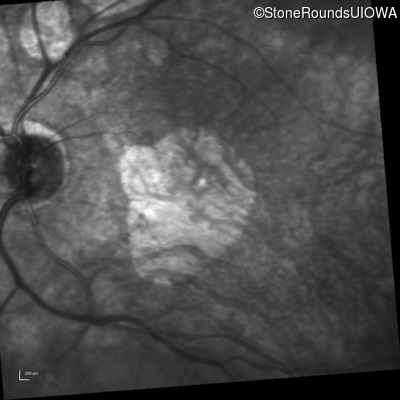

Infrared Fundus Photograph - Right - 20/100

Exemplar